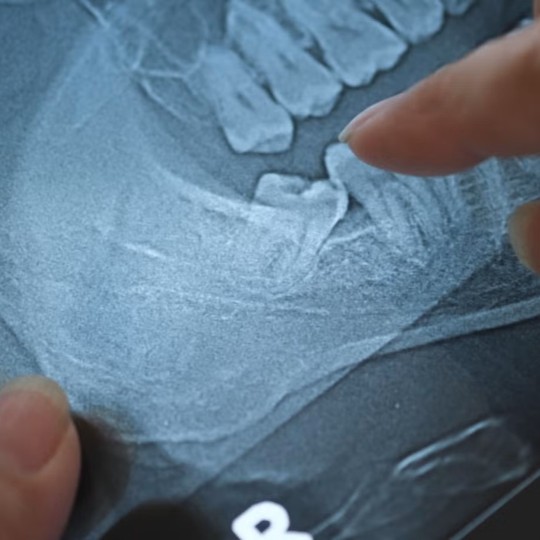

Wisdom teeth that don’t come all the way into the mouth and remain impacted are at risk for developing cysts or tumors. Wisdom teeth are very far back in the mouth, making them hard to monitor using small dental X-rays, so tumors and cysts around wisdom teeth can become pretty decent-sized before they’re identified. And even when they’re benign, they can cause damage. Some patients don’t want to have to monitor their wisdom teeth for this.

There’s also a procedure called a coronectomy, which is removing the top part of the tooth (the crown) and leaving the roots behind. We do that for patients who are at high risk for a nerve injury, which we would be able to see on an X-ray. This procedure is less likely to cause permanent nerve injury than a full extraction.